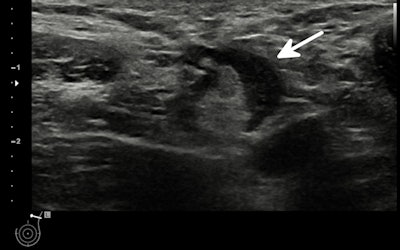

- In patients without breast cancer history and no suspicious breast imaging findings, imaging-detected unilateral axillary lymphadenopathy on the same side of recent COVID-19 vaccination (i.e., within 12 weeks) should be managed according to the clinical setting. In asymptomatic patients, it should be classified as a benign finding (BI-RADS 2) and no further workup should be pursued. In case of patients reporting symptoms of axillary lymphadenopathy more than 12 weeks after vaccination, ultrasound examination of the axilla is recommended. In patients with axillary symptoms, incidental unilateral axillary lymphadenopathy ipsilateral to the vaccination side without any suspicious finding in the breast should be classified as a probably benign finding (BI-RADS 3), requiring a 12-week follow-up. In case of persistent suspicion at this 12-week follow-up, ACR BI-RADS recommendations for the management of axillary lymphadenopathy should be followed, with further workup including, when necessary, tissue sampling.